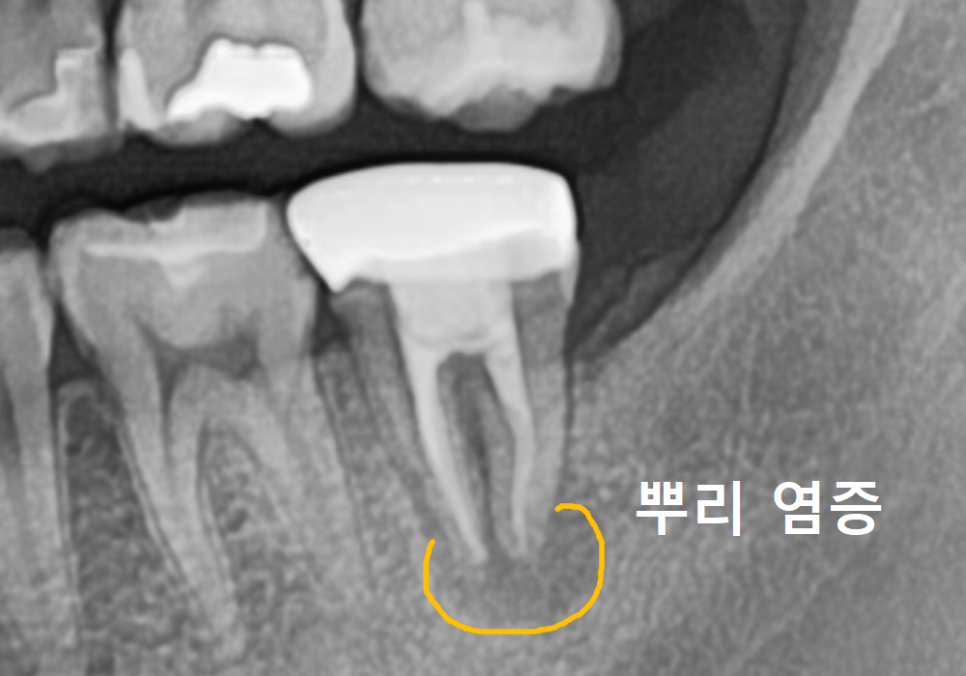

얼마 전 1년 전 신경치료를 받았던

오른쪽 아래 어금니(#37) 문제로

한 환자분이 내원하셨어요.

260219

뿌리 염증 때문에 타병원에서

발치 후 임플란트 권유 받으셨다고 하는데,,

환자분이 아직 너무 젊으셨어요.

임플란트하기엔 너무 아까운 나이.. ㅠㅠ

CT상에서도 뿌리 염증이 꽤 진행되어 있었지만,